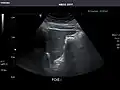

Abdominal Ultrasound (Full Exam)

STRUCTURED REPORT

(Technique: Transabdominal ultrasonography; Device: Toshiba Aplio XG)

Liver: Diffusely homogeneous and normal in echogenicity. No focal mass or contour nodularity. No intrahepatic biliary ductal dilatation.

Portal Vein: Patent main portal vein.

Gallbladder: No stones, wall thickening, or pericholecystic fluid.

Common Bile Duct: Nondilated measuring 1.3 mm at the level of the porta hepatis.

Pancreas: Visualized portions unremarkable.

Spleen: Normal in size.

Kidneys: Right and left kidneys measure 11.5 cm and 12 cm in length respectively. No hydronephrosis. Small left lower pole kidney cyst.

Ascites: None.

Aorta: Visualized portions normal in caliber, 16 x 15 mm.

IVC: Normal.

IMPRESSION:

Normal abdominal ultrasound.